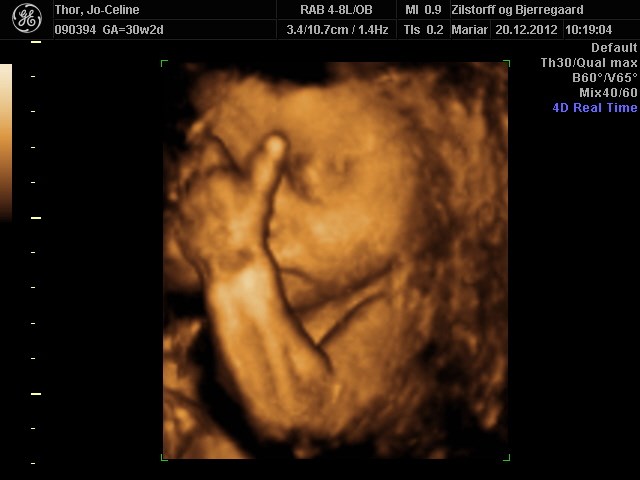

Søger man på Google kommer der kun 3D-billeder.

Så jeg vil høre om nogen herinde har et billede eller to fra uge 28 de vil vise? Og hvor lang var jeres baby, og fik I vægt at vide?